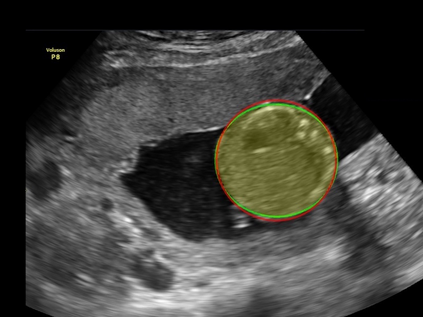

In this paper, we propose an end-to-end multi-task neural network called FetalNet with an attention mechanism and stacked module for spatio-temporal fetal ultrasound scan video analysis. Fetal biometric measurement is a standard examination during pregnancy used for the fetus growth monitoring and estimation of gestational age and fetal weight. The main goal in fetal ultrasound scan video analysis is to find proper standard planes to measure the fetal head, abdomen and femur. Due to natural high speckle noise and shadows in ultrasound data, medical expertise and sonographic experience are required to find the appropriate acquisition plane and perform accurate measurements of the fetus. In addition, existing computer-aided methods for fetal US biometric measurement address only one single image frame without considering temporal features. To address these shortcomings, we propose an end-to-end multi-task neural network for spatio-temporal ultrasound scan video analysis to simultaneously localize, classify and measure the fetal body parts. We propose a new encoder-decoder segmentation architecture that incorporates a classification branch. Additionally, we employ an attention mechanism with a stacked module to learn salient maps to suppress irrelevant US regions and efficient scan plane localization. We trained on the fetal ultrasound video comes from routine examinations of 700 different patients. Our method called FetalNet outperforms existing state-of-the-art methods in both classification and segmentation in fetal ultrasound video recordings.